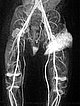

Kontrastmittelunterstützte, dynamische MR-Angiographie (koronare Schichtführung).

30 s nach KM-Injektion in der früharteriellen Phase kommt es zu einem sofortigen, frühen Enhancement des Tumors in der linken Leiste.

41 s nach KM-Injektion in der spätarteriellen Phase kommt es zu einem weiteren, eher diffusen, starken Enhancement des Tumors („tumor-blush“) in der linken Leiste, entsprechend einem soliden Gefäßtumor.

57 s nach KM-Injektion in der frühen venösen Phase reichert der gesamte Tumor weiterhin stark an. Es kontrastiert sich jetzt auch eine im Seitenvergleich stark erweiterte frühe Drainagevene. Durch die starke Tumorperfusion mit erhöhtem venösen Abstrom hat sich die venöse Drainage (Venae iliacae links) dilatiert.

130 s nach KM-Injektion in der späten Phase bleibt das starke Enhancement des Tumors in der linken Leiste erhalten, kein frühes „wash-out“. Auch die erweiterte venöse Drainage über die linken Iliakalvenen kontrastiert nach wie vor.